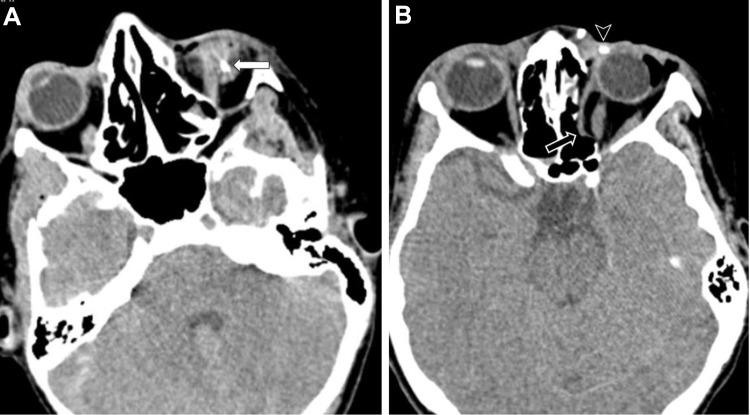

To report the type and severity of ocular injuries sustained by the survivors of a bomb-loaded explosion that occurred in Mogadishu, Somalia on December 28, 2019.

After the explosion, ocular injuries were detected in 28 of 114 patients in our hospital. Thirty-two eyes of 28 patients were included in the study. The mean age was 32.4±6.7 years. The number of open-globe injuries was more than that of closed-globe injuries (26 vs 6; 81.25% vs 18.75%, respectively). Zone 1 was the most affected zone in open-globe injuries (18/26 eyes, 61.6%), followed by Zone 3 in six (23%) patients and Zone 2 in four (15.4%) patients. Sixteen open-globe injuries were laceration type (61.5%) and 10 (38.5%) were rupture type. An intraocular foreign body was detected in eight (30.8%) eyes with open-globe injuries. A total of 28 patients had 11 (39.3%) isolated eye injuries, whereas 17 (60.7%) had concomitant systemic injuries.